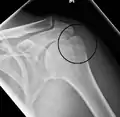

Proximal humerus fracture

A transverse fracture of the humerus shaft